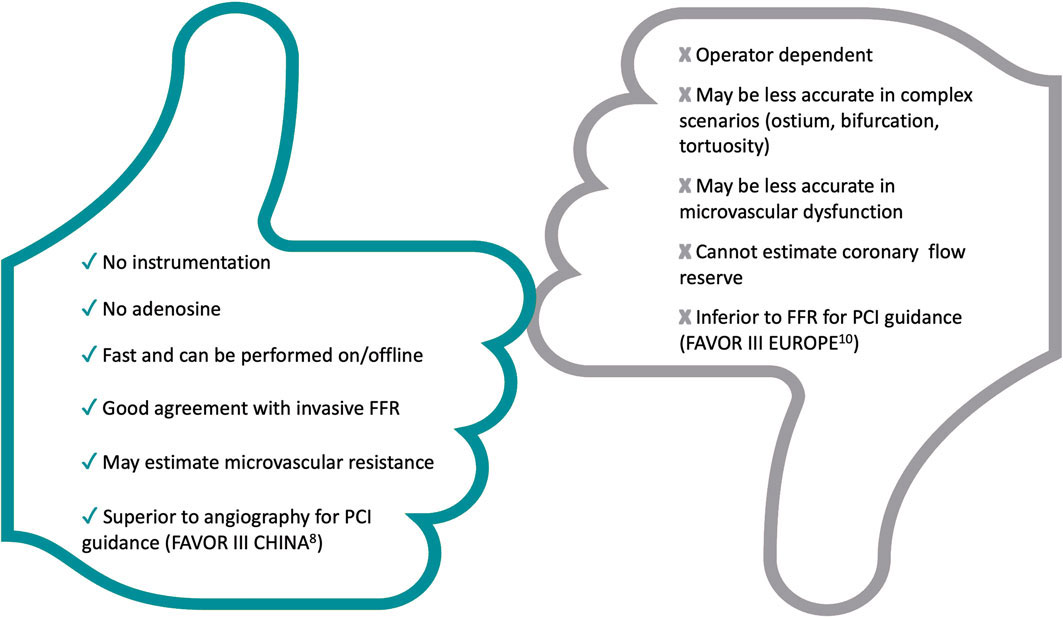

Técnicas de evaluación fisiológica derivadas de la angiografía: ¿todavía tienen cabida después de la publicación del ensayo FAVOR III Europe?

Artículos originales

Artículos de revisión